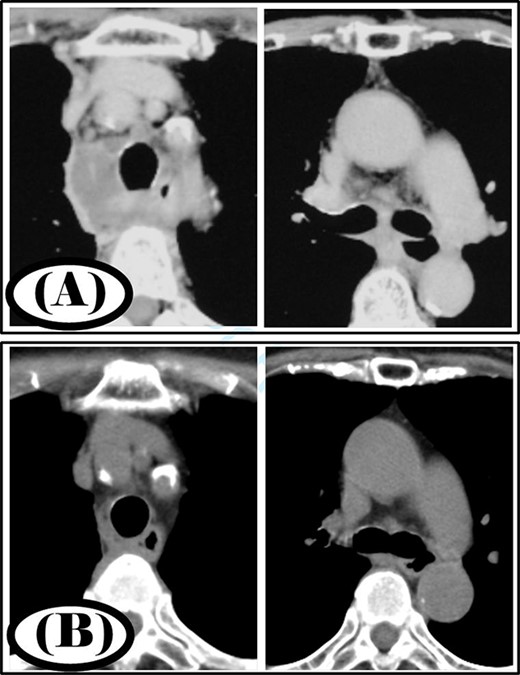

A 77-year-old woman had a chief complaint of sore throat and was diagnosed with a retropharyngeal abscess. Cervicothoracic computed tomography (CT) showed that the infection had spread to the mediastinum (Fig. 1A). The patient was diagnosed with type IIB DNM. Cervical drainage and mediastinal drainage through the cervical approach were performed on the day of admission. Staphylococcus epidermidis, Streptococcus mitis and Acinetobacter lwoffii were detected in the mediastinal abscess cavity. The patient was administered ampicillin/sulbactam at 12 g/day for 3 weeks. Continuous irrigation with saline (2 l/day) was initiated immediately post-surgery. The duration of irrigation, drainage and hospital stay were 4, 10 and 30 days, respectively. Four weeks post-surgery, cervicothoracic CT showed no abscess cavity and the infection had improved (Fig. 1B).

Case 1: pre- and post-treatment cervicothoracic CT; (A) pre-operative cervicothoracic CT and (B) cervicothoracic CT 4 weeks after treatment.